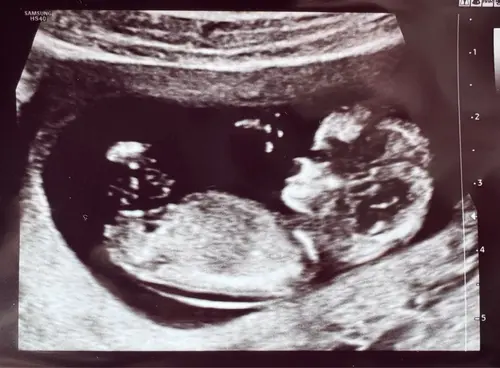

Aahw , ja dit is de mijne maar zn nekploi is te hoog, die van jullie zien er idd annders uit🥺

Ik mag geen nipt test meer doen omdat 3.7 van de eerste echo, te hoog is voor een nipt😬